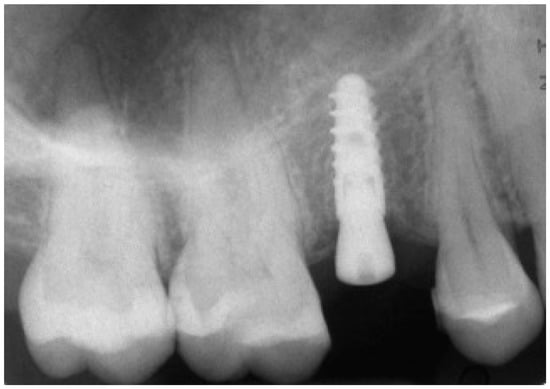

At 1 year year after placement, all 36 implants were regularly functioning, for a survival rate of 100% (36/36 implants surviving) (Figure 15).

Figure 15.

One-year follow-up rx control of the implant supported crown.